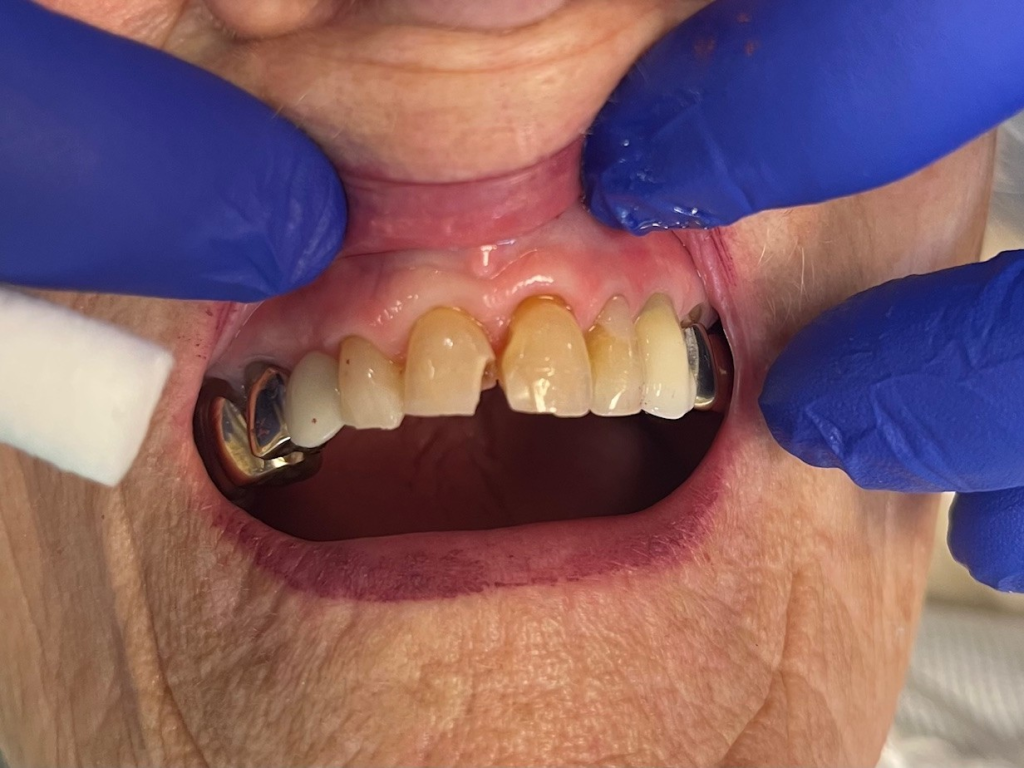

Anterior broken tooth. Double DentXpinTM repair.